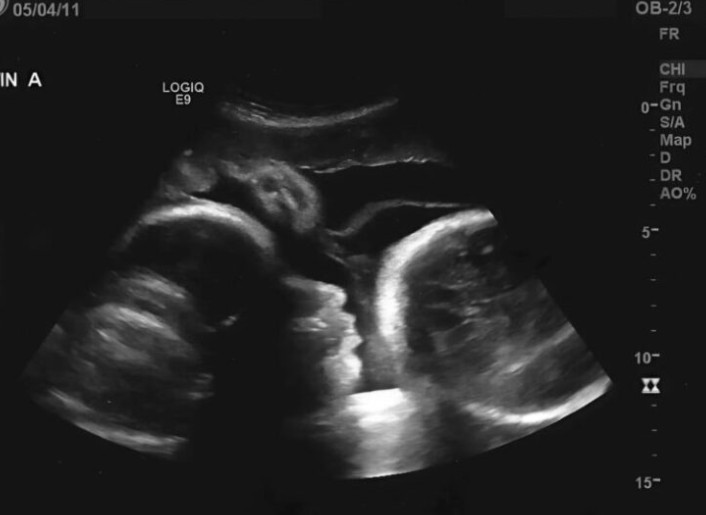

Kiedy doktor spojrzał na ekran ultrasonografu, jego twarz nagle pobladła, a bolesna prawda wydostała się z jego ust drżącym głosem. Larisa nie była w ciąży – pierwsze testy dały tragicznie mylny wynik. Przyczyną rosnącego brzucha starszej kobiety nie było nowe życie, lecz gigantyczny guz jajnika, który powoli trawił jej organizm od środka.

Słowa lekarza były dla Larisy druzgocącym ciosem. To, co brała za „ruchy dziecka”, było w rzeczywistości uciskiem nowotworu na jej narządy wewnętrzne. Co gorsza, przez tak długą zwłokę w szukaniu pomocy medycznej, komórki rakowe rozprzestrzeniły się po całym ciele. „Gdyby przyszła Pani na początku, moglibyśmy Panią uratować, ale teraz sytuacja jest krytyczna” – wyznał lekarz, rzucając jej w twarz gorzką prawdę.